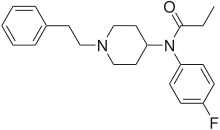

Anilidopiperidines

Phenylpiperidines